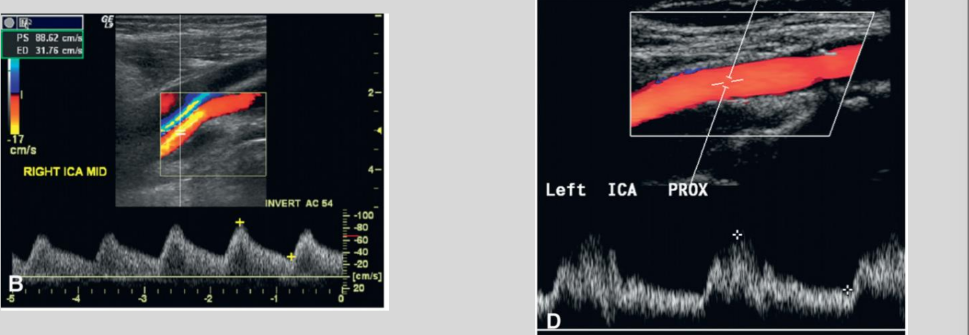

◦ Aortic Valve Insufficiency

Pulsus Bisferiens: double systolic peak

◦ Measure the first peak

◦ Diminished end diastole

◦ Difference between an ICA occlusion & aortic valve insufficiency is

that the occlusion is typically unilateral

what waveform is this

Aortic Insufficiency